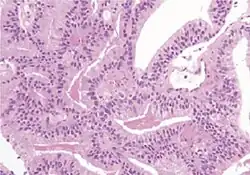

Example histopathologic preparation after prostatectomy.